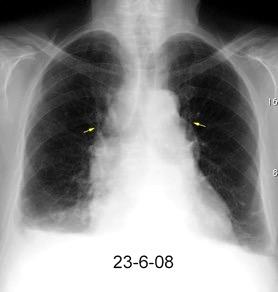

Ganglios retroperitoneales (flechas negras)

germinales del testículo izquierdo Nódulos pulmonares múltiples. (flechas verdes). Ganglios paratraqueales. (flechas amarillas). Dudoso ensanchamiento retrocrural (flechas negras)

Panda A et al. “Straddling Across Boundaries”. Thoracoabdominal Lesions: Spectrum and Pattern Approach. Curr Probl Diagn Radiol, 2015